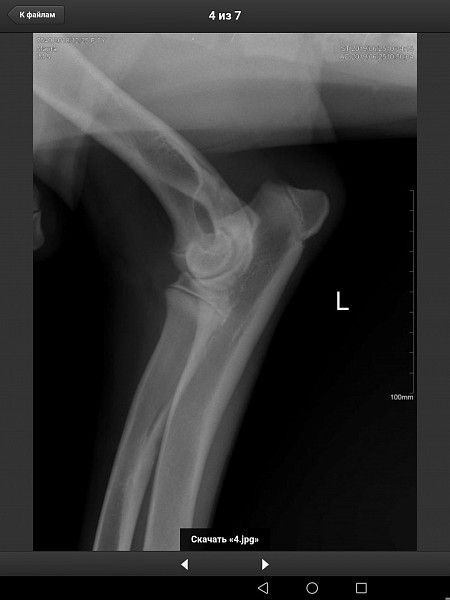

У нас немецкий дог, девочка, 6 месяцев, привита по возрасту. Поставлен диагноз Расслаивающий остеохондрит плечевого сустава (мышь плечевого сустава). Сказали, нужна операция по зачищению этого сустава. Как можно скорее.

Есть рентгеновский снимок. Прошу вас прокомментировать его, правильный ли диагноз? Как срочно нужно оперировать, если подтвердится диагноз? Какой период реабилитации? И, что нас ожидает в будущем, от чего могла развиться болезнь, наследственное это или нет, что делать, чтобы предупредить заболевание суставов других лап?

Здравствуйте. Судя по описываемым вами симптомам у собаки, действительно имеется поражения хрящевой поверхности какого-то сустава грудой конечности. На предоставленных вами снимках, затруднительно тщательно рассмотреть суставные поверхности. Ярко выраженной патологии хряща (расслаивающий остеохондрит не просматривается). Для подтверждения или исключения данной патологии наиболее оптимальным является компьютерная томография. При подтвтерждении диагноза, основным методом лечения является хирургическое вмешательство, направленное на устранение фрагментированного участка хряща и зачищении дефекта для формирования на месте поражения волокнистого хряща.